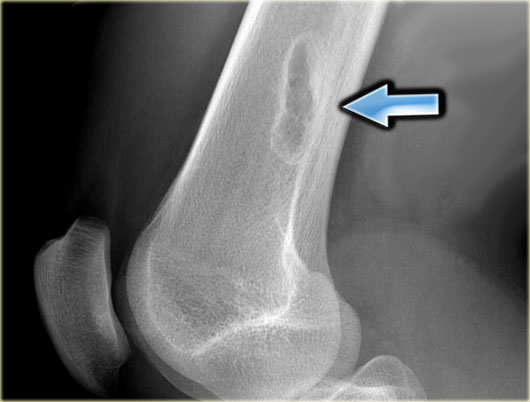

X-ray an CT-image of a typical osteoid osteoma in the proximal tibia.

Notice the sclerotic center within the osteolytic lesion (red arrow).

MR-images of the same patient demonstrate cortical thickening and extensive edema.